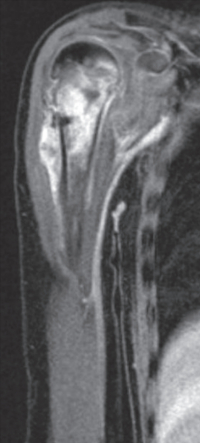

血液所見:赤血球 468万、Hb 13.9 g/dL、白血球 4,300、血小板 18万。血液生化学所見:総蛋白 7.5 g/dL、アルブミン 3.9 g/dL、総ビリルビン 0.9 mg/dL、直接ビリルビン0.2mg/dL、AST 28 U/L、ALT 16 U/L、LD 177 U/L(基準 120~245)、ALP 566 U/L(基準 38~113)、γ-GT 32 U/L(基準 8~50)、CK 42 U/L(基準 30~140)、尿素窒素 12 mg/dL、クレアチニン 0.3 mg/dL、尿酸 4.9 mg/dL、Na 136 mEq/L、K 4.4 mEq/L、Cl 97 mEq/L。CRP 0.9 mg/dL。右上腕骨の単純エックス線写真とMRIの脂肪抑制造影T1強調冠状断像を別に示す。